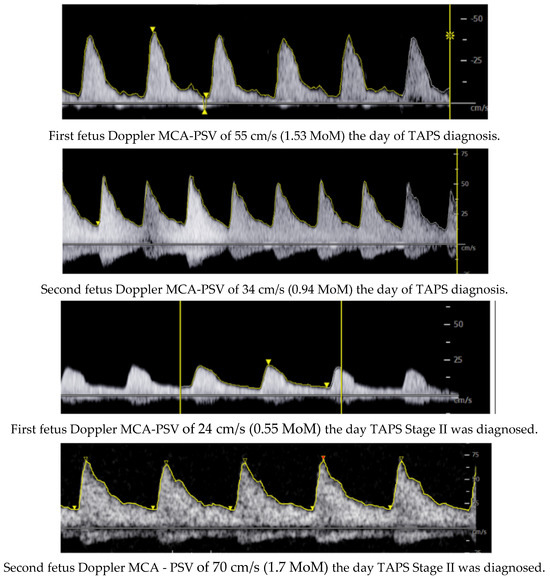

During her stay, a control ultrasound at week 27 + 5 revealed the following: the first fetus had an estimated fetal weight (EFW) of 1073 g (27th percentile), a PSV of 55 cm/s (1.53 MoM), a normal UA PI, a visible bladder, and normal AFV; the second fetus had an EFW of 1221 g (74th percentile), a PSV of 34 cm/s (0.94 MoM), a normal UA PI, a visible bladder, and normal AFV. The placenta was located on the posterior wall with discordant echogenicity (Figure 1). Given the findings and the suspicion of TAPS, the case was presented to the multidisciplinary perinatology committee, and it was decided to follow up with ultrasound monitoring twice a week for evaluation.

In Figure 2, we can observe the evolution of both the PSV and the delta value during subsequent follow-up assessments.

Figure 2. Evolution of PSV and delta value.

Following the ultrasound values observed at week 31 + 2 (02/27), the first fetus had an MCA-PSV of 24 cm/s (0.55 MoM) with no signs of cardiac compromise, and the second fetus had an MCA-PSV of 70 cm/s (1.7 MoM) with no signs of cardiac compromise, with a delta MCA-PSV value of 1.1 (Stage II).

Figure 3. Doppler ultrasonography of evolution of MCA-PSV of the twins.